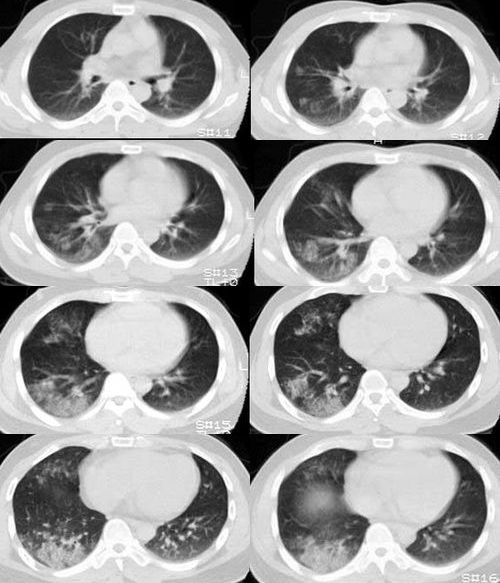

球形肺炎是大叶性肺炎的一种特殊表现[1],以肺的渗出实变为主。它的机理未明,可能是由于抗生素的广泛应用,大叶性或节段性肺炎发展受到限制而形成球形,其形成又与病缘菌的毒性数量及机体的免疫能力有关。病人多有感然症状,某些病人无明显感然症状。病变呈球形或椭圆形,大小不等,病灶密度多均匀,ct值稍低于软组织密度;或中央密度高,边缘密度低,显示晕圈状改变;有时可见空洞[2]。病灶边缘比较规则,也可不规则,有毛刺或呈锯齿状改变,但较模糊。位于肺周区,贴近胸膜,部分病栽表现为两侧缘垂直于胸膜,呈刀切样平直边缘。病灶周围血管纹理增多、增粗、常有局限性胸膜增厚。球形肺炎抗炎两周后,病灶即有缩小,最后能完全吸收。

球形肺炎:病变密度相对较淡,中央密度略高,ct图片上密度较为均匀,增强中央可出现无强化区。病变邻近胸膜反应较为显著,可表现为增厚、粘连(可以比较广泛),病变内可以见到大血管的贯穿,周围及近肺门侧可以见到血管纹理增多、增粗,可有支气管充气征象,两侧可垂直于胸膜或呈方形,边缘可为刀切征,它可以出现毛刺样的类似改变,短期内抗炎治疗有效。